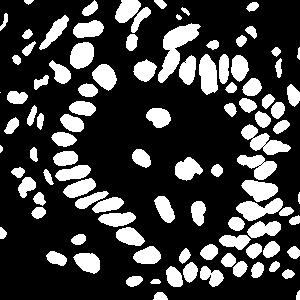

5.3.3 Results and discussion

(a) image

(b) true mask

(c)

Cluster only

(d)

(e)

(f)

(g)

Voronoi only

The effects of two types of labels

In order to explore how the two types of generated labels work on the model training, we change the values of in Eqn. (6). As changes from 0 to 1, all four metrics increase in the beginning and then decrease (shown in Fig. 6). Compared to the results using only the cluster labels (), those with Voronoi labels () are better in the object-level metrics, but worse in pixel-level metrics. This is because the model trained with Voronoi labels predicts the central parts of nuclei, resulting in small separated instances (Fig. 5(g)). While lacking the Voronoi edge information, the model using cluster labels is not able to separate close nuclei (Fig. 5(c)). In contrast, segmentation results using both labels (Fig. 5(d)-(f)) are better than those with either label alone, because they have both the shape information from the cluster label and the nuclei/background information from the Voronoi label. The best performance is achieved when is around 0.5, thus we set for all subsequent experiments.